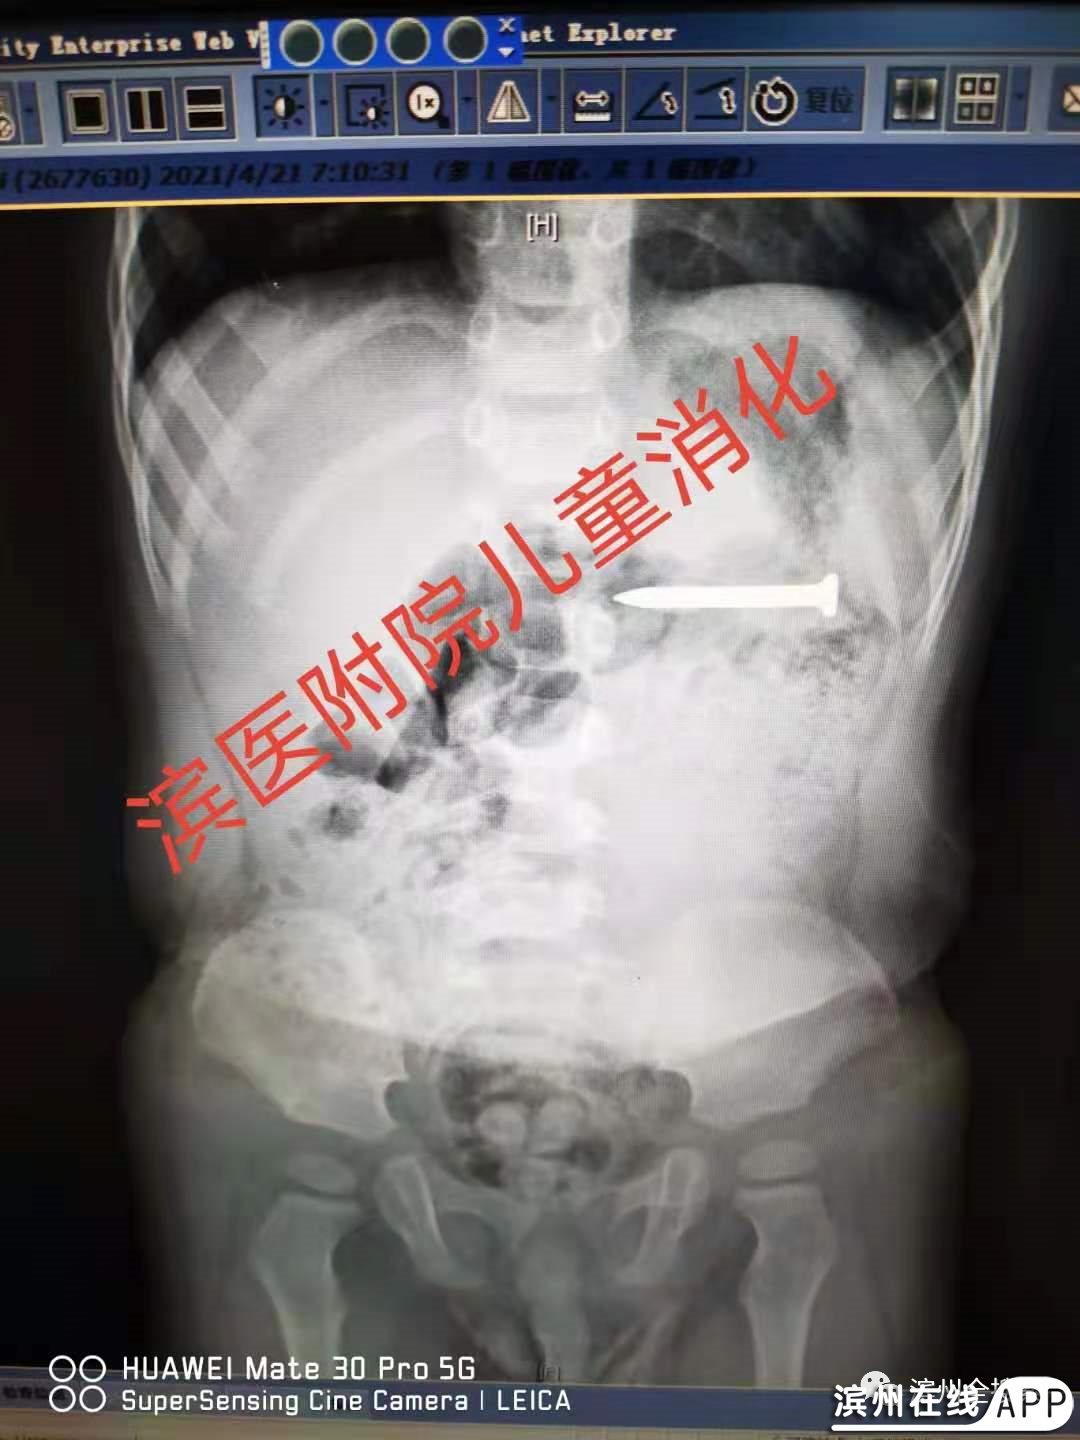

事发滨州!1岁半孩子吞下近4cm的铁钉!

太惊险!!!1岁半孩子把长近4cm的铁钉吞下!!!进镜后胃内没有发现异物,只见黏膜划伤,继续进镜,在十二指肠发现铁钉由于比较尖锐,操作需要格外小心,历经近半小时顺利将其取出,患儿转危为安,避免了胃肠穿孔的风险!